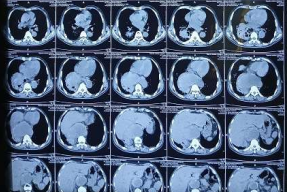

In the subsequent visit, his cough was persisted though fever subsided. His repeat Chest X-ray showed similar right lower lobe dense opacity resembling mass lesion, whereas his sputum reports were negative for M.Tb and sputum culture showed pseudomonas. In suspicion of lung mass, non-contrast CT thorax scan was done and it was found lateral part of ascending thoracic aorta protruded in right lower lobe as aneurysmal sac and surrounded by necrotising consolidation. His sputum was repeated for CBNAAT test and this time found positive for M.Tb, he was started for drug-sensitive Tb regimen and sputum sample sent for M.Tb culture and DST

Fig 3: CT – Thorax Mediastinal Window

Fig 4: CT – Thorax Lung Window

Fig 5: CT – Thorax Coronal

Figure 3

Figure 4

Figure 5